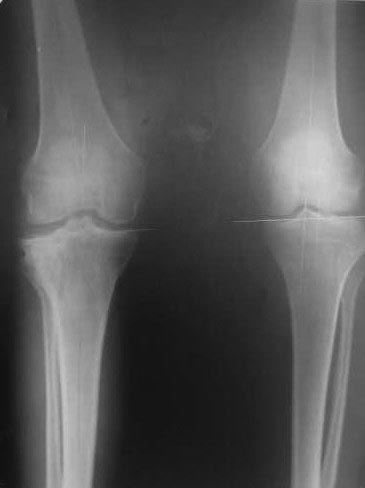

Жалобы на деформацию и нарушение функции правого коленного сустава .Внешний вид –вальгусная деформация на уровне коленного сустава .Коленный сустав стабильный, надколенник при сгибании в правильном положении.

Планируэм провести остеотомию на уровне проксимального метафиза большеберцовой кости .

Большое спасибо за Ваши профессиональные советы .Разрешите задать вопрос иначе . Возможно ли выполнить резекцию по медиальной стороне большеберцовой кости (closing wedge osteotomy) для устранения вальгусной деформации коленного сустава.